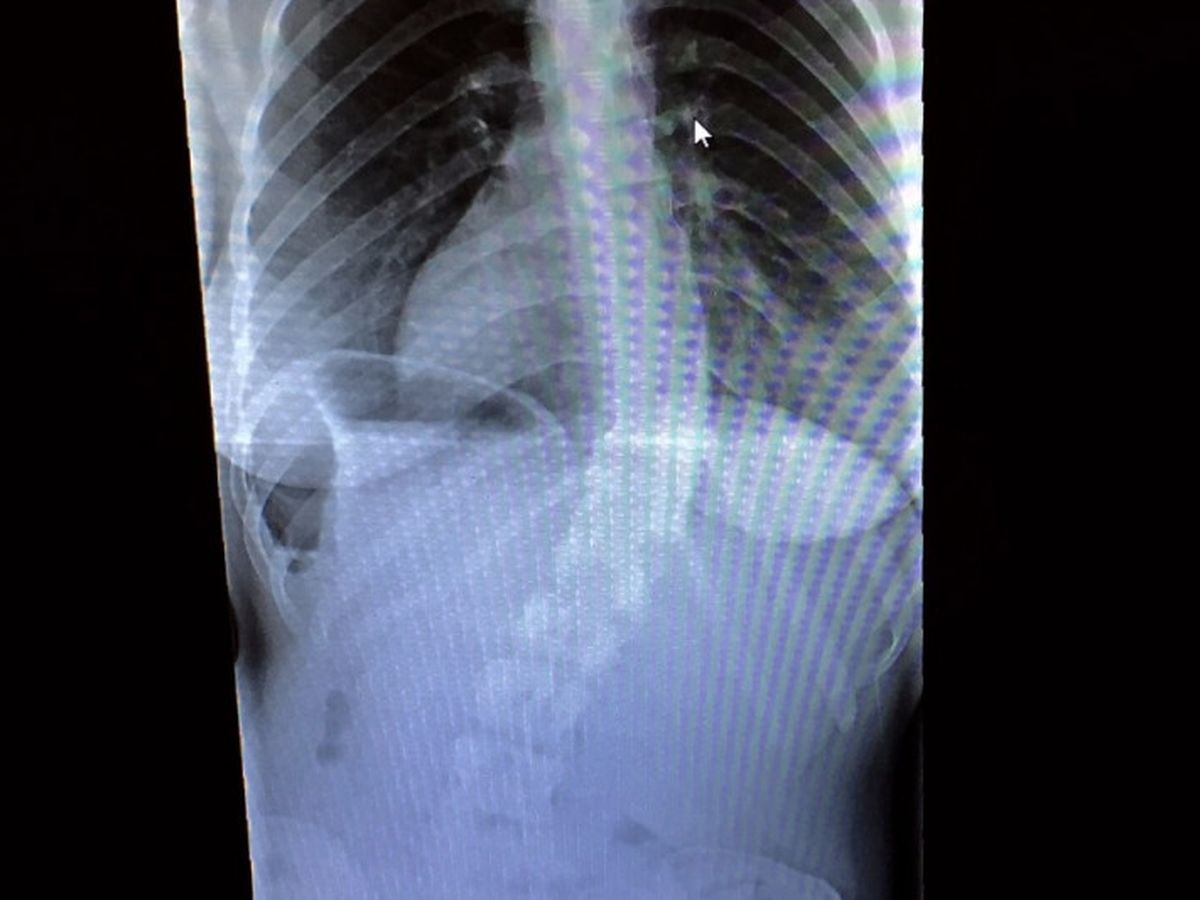

As some of you may know, Allyn has had severe scoliosis her entire life. Six years ago it was discovered that she had a 32 degree curve on her spine. Two months ago she had more x-rays taken along with MRIs that showed an increase in the curve to 47 degrees, making it a mandatory surgery. Though she may seem fine from her appearance, this degree of scoliosis is extremely painful which makes it difficult to go about her day to day activities.